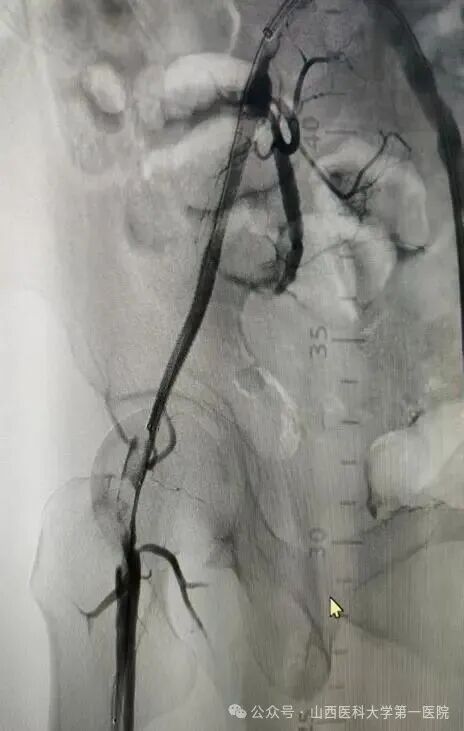

52岁王先生有长期高血压、糖尿病史,且未规范治疗控制,长期吸烟饮酒,饮酒量每日1斤左右,近年来逐渐出现间歇性跛行症状。10月20日凌晨,王先生突发右下肢发冷疼痛,当地医院下肢血管超声提示右侧髂动脉、股总动脉、腘动脉闭塞,紧急转诊至山医大一院血管外科。入院时患者右足发绀、皮温差,右足运动感觉明显减退,患侧股动脉、腘动脉、胫后动脉、足背动脉均无法触及搏动,这种急性髂股动脉血栓形成病情十分危急,死亡率40%以上,随时面临截肢与生命危险。

患者的全身状况同样堪忧,心肝肾功能异常,感染指标显著升高,“必须立刻打通血管,同时兼顾全身多器官的保护,既要保命,更要尽最大努力保肢,守护患者的生活尊严。”王贵明主任第一时间带领团队制定救治方案。为患者紧急实施了右髂动脉覆膜支架植入、球囊扩张成形及机械血栓清除等手术,成功恢复下肢血流。然而术后危机接踵而至:患者出现右小腿骨筋膜室综合征,骨科贾二龙主任医师紧急会诊后为其施行筋膜切开减压及负压封闭引流术;术后患者转入ICU,又相继出现急性肾衰竭、严重低蛋白血症、电解质紊乱、重度营养不良、发热及急性心衰等多重挑战,重症医学科与血管外科密切配合研判病情,通过抗凝、抗感染、营养支持、纠正心衰、连续性血液净化等一系列综合治疗,患者病情逐渐平稳。两周后转回普通病房,但肾功能仍未恢复。王贵明、马宏刚、刘唯棕组织全院大会诊,围绕透析管理、心功能维护、骨筋膜室综合征术后康复等制定后续方案。在肾内科、心血管内科、临床营养科等科室的共同配合下,患者全身状况日渐稳定。